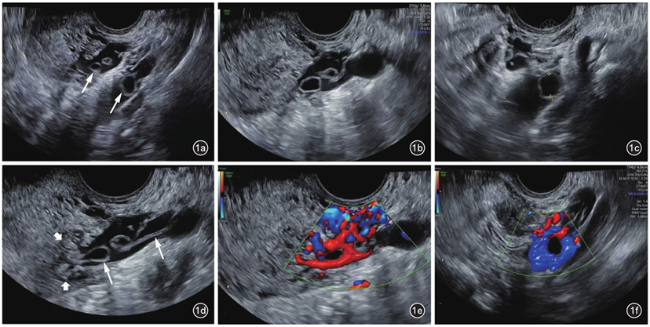

图2 盆腔静脉侵袭性葡萄胎患者化疗前盆腔MRI T2加权横断面成像。图a示子宫左侧宫旁静脉迂曲增粗,内见数个囊状结构(箭头所示);图b示左侧扩张髂静脉内见囊泡状结构(箭头所示)

入院妇科查体左附件区呈增厚感,无压痛,右附件区未见异常。经阴道超声检查显示子宫宫腔内可见支架回声,内膜菲薄,左侧壁上段临近浆膜层处肌层回声不均,局部可见团块状中高回声,大小1.4 cm×1.3 cm;左侧宫旁静脉及髂静脉显著扩张,最宽处达到1.4 cm,内部可见多个薄壁囊泡状无回声及条索状的中等回声结构,其中较大的无回声直径约为0.9 cm。动态观察显示子宫左侧壁上段临近浆膜层处中高回声与宫旁扩张静脉内异常回声相连。双侧附件区未见明确囊实性包块。彩色多普勒血流成像(color Doppler flow imaging,CDFI)显示宫旁扩张静脉及髂静脉的囊泡状无回声内未见血流信号,周边残余管腔血流充盈尚可(图1)。超声检查提示子宫肌层及左侧盆腔静脉内异常回声,结合临床考虑侵袭性葡萄胎可能。盆腔动态增强MRI显示子宫左侧壁上段可见小囊状长T2信号,邻近伴多发迂曲略粗血管流空信号;左侧附件区可见不规则小片状等T2信号及多发小囊状长T1长T2信号,强化不均,邻近宫旁静脉迂曲增粗呈蚓状,范围约4.4 cm×1.7 cm,提示左侧附件区及子宫左侧壁上段见多发异常信号及血管流空影,妊娠滋养细胞肿瘤不除外(图2)。患者胸部CT、心脏超声、心电图未见明显异常。